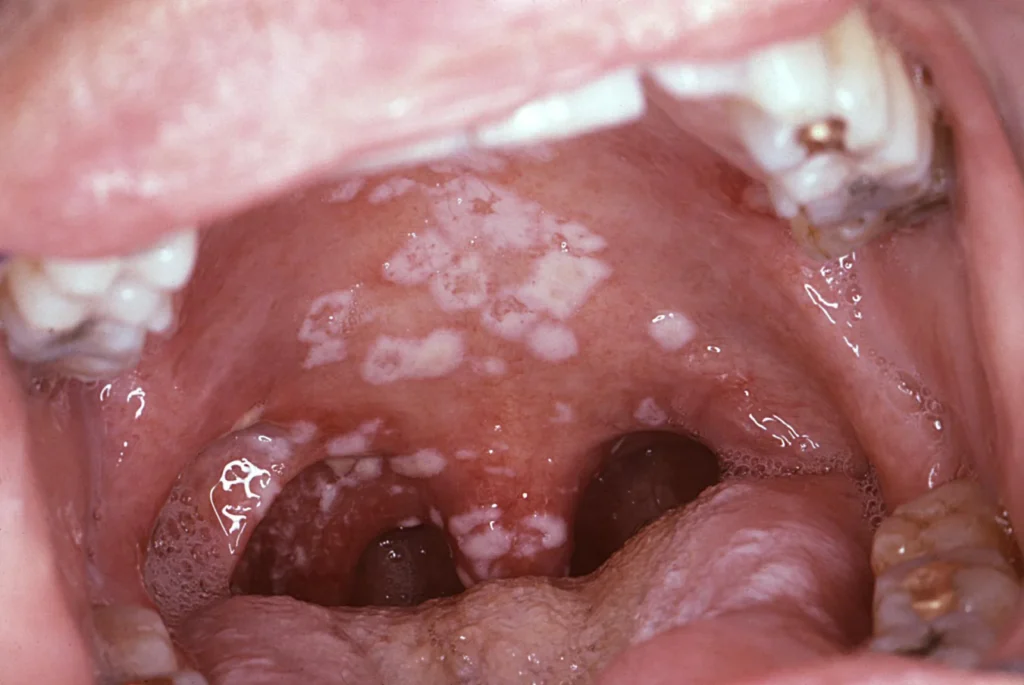

Oral Thrush: Causes, Symptoms, Diagnosis & Treatment Options

Oral thrush, also known as oral candidiasis, is a common fungal infection that affects millions of people every year. According to the Centers for Disease Control and Prevention (CDC), Candida species are present in the